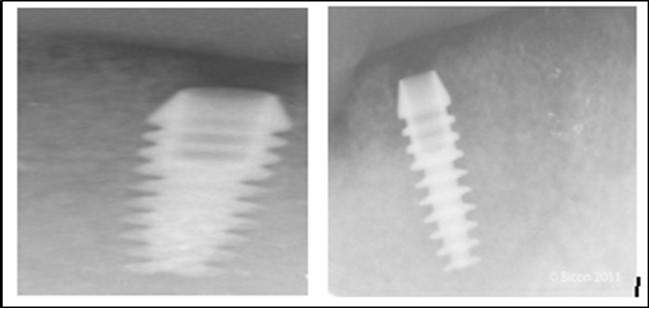

Post operatively after 3 months, osseointegration was evaluated clinically and radiographically (Figure 5a,b) and the implants were well prepared to receive the prosthesis. The second stage surgery was performed in which cover screws were removed and healing abutment were inserted into the implants (Figure 6). After a time period of two weeks, peri-implant soft tissue healing was examined, and existing denture was relined after relieving at the abutment site. Later, the healing abutment is removed using a 1.25 mm hex driver. Internal portion of the implant is irrigated and dried to make sure if it is free of debris and soft tissue. A periodontal probe was used to measure the gingival cuff height at the right and left canine site of implant location. Selected ball abutment were placed onto each implant using 1.25 mm hex driver and 30 Ncm torque wrench (Figure 7A).

Figure 5.a,b. Post-insertion radiographics in the mandibular area right,left,

a,b. Post-insertion radiographics  in the mandibular area right,left,

Figure 6.Panoramic radiograph after the insertion of two implants

Panoramic radiograph after the insertion of two                 implants